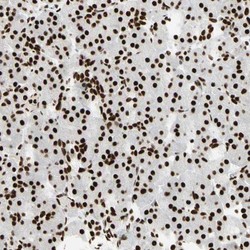

NBP1-86626 IHC

Immunohistochemistry